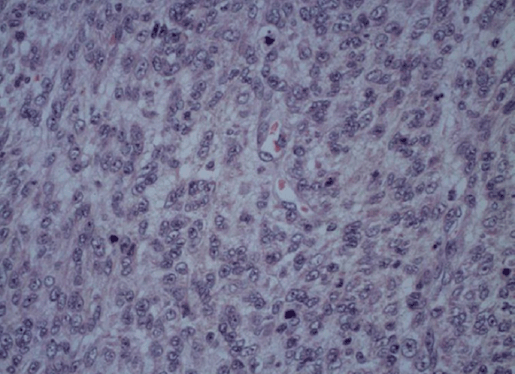

Pelvic ultrasound showed a globular uterus with irregular contours, containing multiple intramural myomas. Pelvic computed tomography (CT) scan confirmed the findings of multiple intramural myomas with one large 10x8 cm posterior subserosal myoma, associated with a suspected ovarian cyst measuring 80 mm of diameter (Figure 1).

Figure 1: Post-contrast pelvic computed tomography scan showing enlarged myomatous uterus.